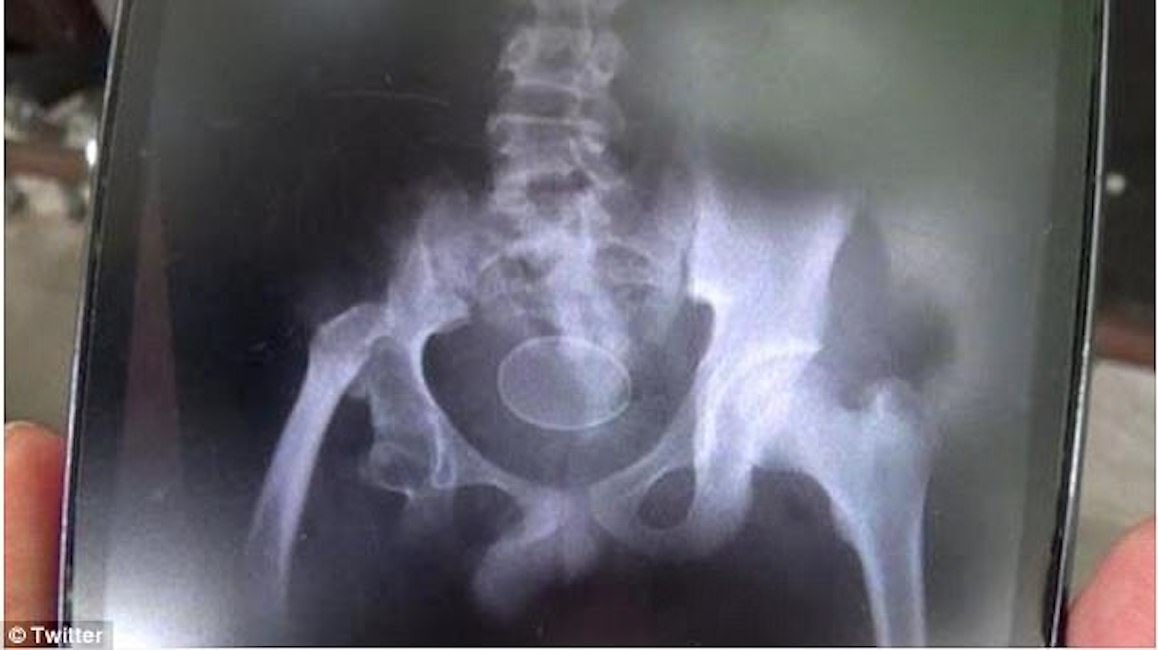

GIACARTA – Un caso unico quanto sconcertante: a Gowa, Indonesia, il 14enne Akmal avrebbe deposto regolarmente dal 2016 a oggi, ben 20 uova. Secondo il padre Rusli, Akmal è stato ricoverato più volte in ospedale, recentemente ha deposto 2 uova in presenza dei medici e ogni uovo contiene solo il tuorlo o solo albume.

I medici sono perplessi, sostengono sia impossibile che delle uova si formino all’interno del corpo umano, scrive il Daily Star. Un portavoce dell’ospedale ha detto: “Il nostro sospetto è che le uova siano state deliberatamente spinte nel retto di Akmal. Ma non l’abbiamo visto direttamente”.